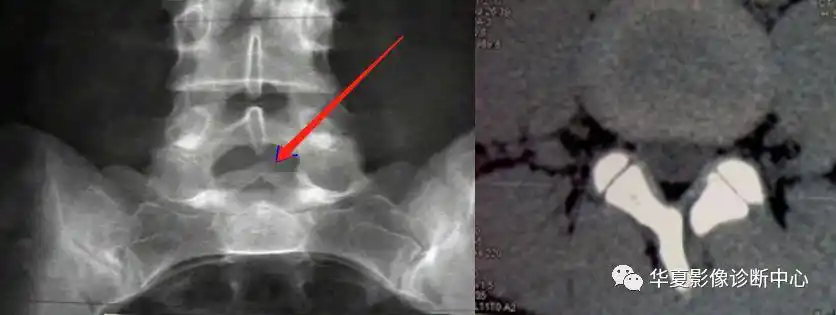

隐形脊柱裂的腰骶椎隐裂生理病理表现

温故知新脊柱裂的分型

小儿先天性脊柱裂的临床诊治

先天性脊柱裂常见类型及手术对策专家共识2016版